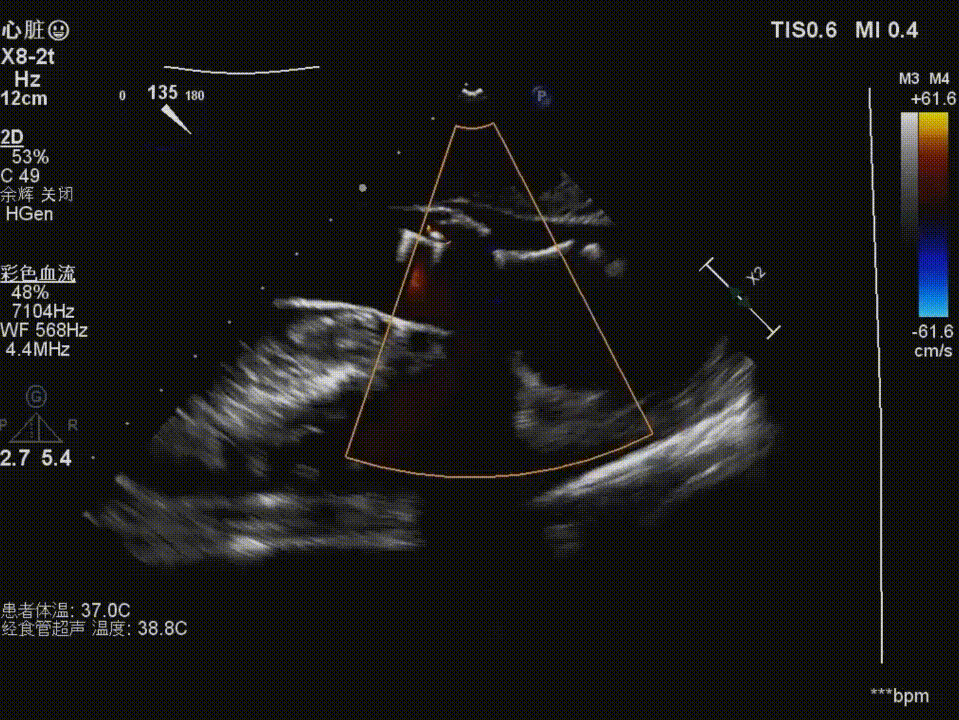

复查造影及食道超声示瓣膜位置,形态满意,瓣周漏较前明显好转,右冠血流恢复,无栓塞迹象;

术后造影

术后食道超声示:

主动脉瓣血流速度及跨瓣压差较术前明显改善,未见明显反流,微量瓣周漏;右冠灌注良好。患者术后恢复顺利,未出现低灌注或心肌缺血相关并发症。